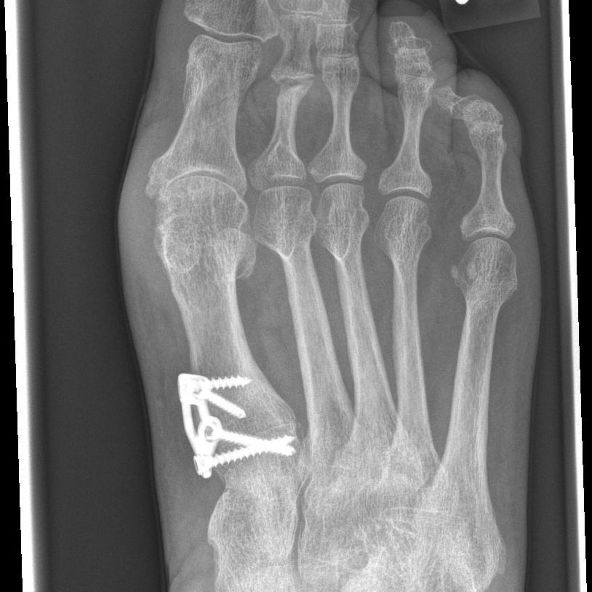

Gemessen an den insgesamt in Deutschland durchgeführten Hallux valgus Operationen, ist dieser Anteil aber verhältnismäßig gering Schmerzen treten bei den meisten Patientinnen und Patienten in normalem Maße auf.

Source: metworkskjx.pages.dev Minimalinvasive Hallux valgus OP Dr.medic Manuel Nastai , In der Regel klingen sie nach ein bis zwei Wochen deutlich ab. Gemessen an den insgesamt in Deutschland durchgeführten Hallux valgus Operationen, ist dieser Anteil aber verhältnismäßig gering

Source: urismancpe.pages.dev 1 Jahr nach Hallux OP Schmerzen Ursachen, Patientenerfahrungen & Lösungen , imago images / Müller-Stauffenberg Maßnahmen zur Schmerzlinderung Die wirksame Schmerzkontrolle nach einer Hallux -OP ist entscheidend, um den Heilungsprozess zu fördern und um Ihnen die Situation zu erleichtern. Gegen die postoperativen Schmerzen in den ersten Tagen nach der OP werden Schmerzmittel verschrieben